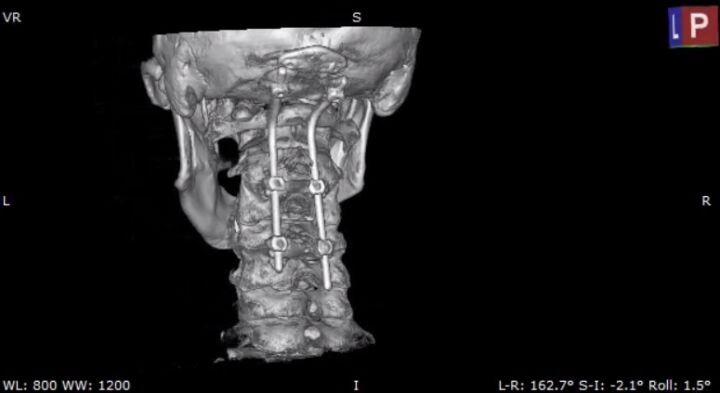

Мужчину госпитализировали. Врачи обследовали шейный отдел позвоночника и выявили перелом второго шейного позвонка (С2) со смещением отломка. Специалисты решили провести операцию — окципитоспондилодез («закрепление повреждённых позвонков верхнего шейного отдела. Позвонки и кости черепа соединяют в единый блок с помощью специальных креплений». — Прим. «Ё!»).

Фото: БУЗ ВО ВГК БСМП № 1